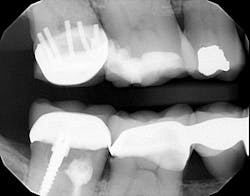

P.S. I counted seven pins.